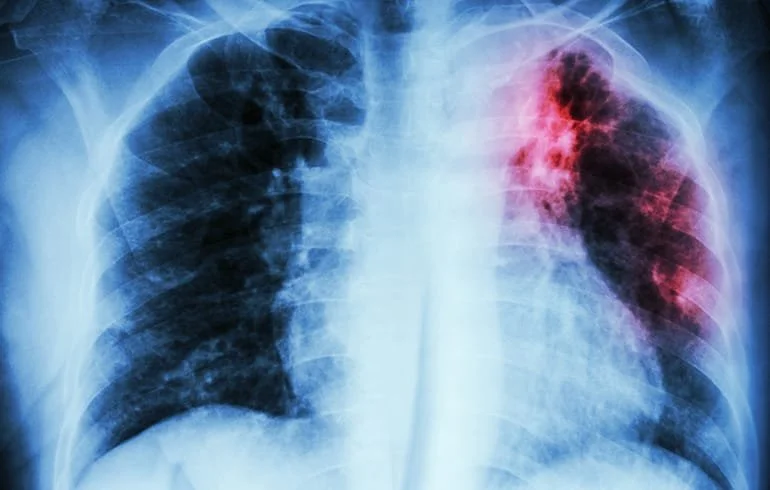

La tuberculosis es una infección bacteriana contagiosa que afecta principalmente a los pulmones, aunque puede comprometer otros órganos. Es causada por la bacteria Mycobacterium tuberculosis. “Esta enfermedad se presenta con síntomas generales y respiratorios inespecíficos, de los cuales los más frecuentes son la tos y la expectoración de más de dos semanas de evolución. También puede presentar compromiso del estado general, fiebre, sudoración nocturna, flema con sangre y baja de peso. No todas las personas que se infectan desarrollan la enfermedad, ya que la gran mayoría controla la infección sin complicaciones. Se estima que alrededor de un 10% de los infectados manifestarán esta patología durante su vida”, precisó Gustavo Rojas Medina, jefe del Departamento de Salud Pública y Planificación Sanitaria.